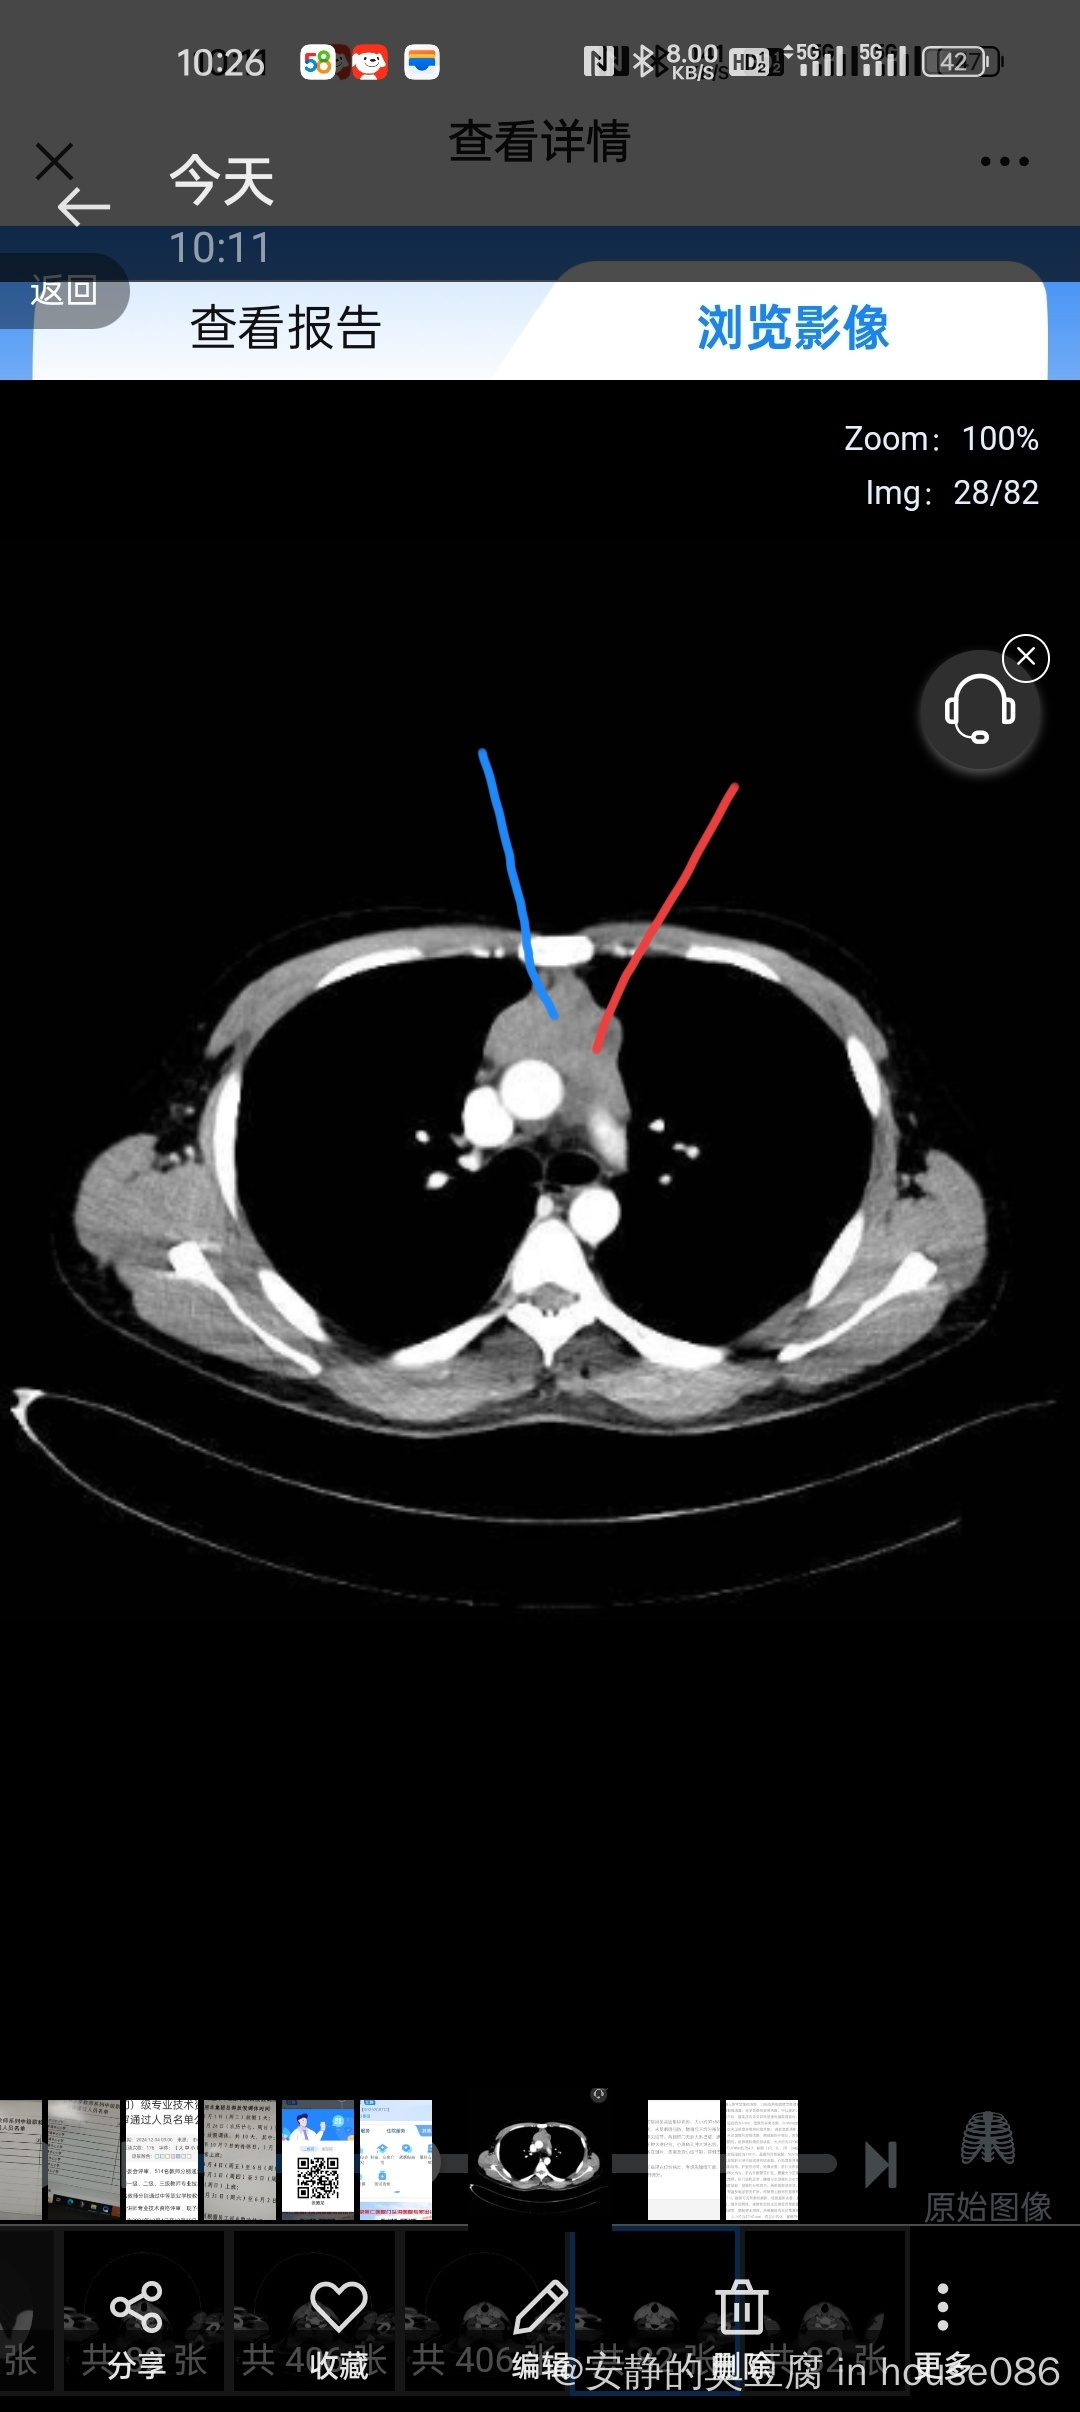

因一个月体检发现前纵膈占位5cm*4cm,复查增强ct,提示胸腺瘤和淋巴瘤可能。

petct提示纵膈肿块suvmax:4.3,纵膈有淋巴结suvmax:3.1,提示恶性肿瘤可能。穿刺四条组织,组织不清。

图片就是两次穿刺角度

检查描述】:前纵隔见类圆形肿块影,大小约33×68mm,平扫密度

不均匀,未见钙化,未见明确脂肪,增强后不均匀强化,与邻近结构边

界欠清,两胸膜未见结节。两侧肺门无肿大淋巴结,纵隔无肿大淋巴

结,两侧锁骨区无肿大淋巴结,心膈角无肿大淋巴结。两肺纹理清晰

走向自然,两肺散在斑片、条索及微小结节影。两侧无明显胸腔积液。

心包无明显积液。